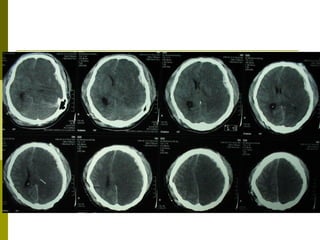

Clasificación Tomográfica del TEC según el National Traumatic Coma Data Bank (TCDB)  Grado, Tipo de lesión, TAC craneal I  Lesión difusa I  Sin patología visible en la TAC II  Lesión difusa II  Cisternas presentes con desplazamientos de la línea media de 0-5 mm y/o lesiones densas presentes. Sin lesiones de densidad alta o mixta > 25 cm3. Puede incluir fragmentos óseos y cuerpos extraños. III  Lesión difusa III (Swelling)  Cisternas comprimidas o ausentes con desplazamiento de la línea media de 0-5 mm. Sin lesiones de densidad alta o mixta > 25 cm3. IV  Lesión difusa IV (Shift)  Desplazamiento de la línea media > 5 mm. Sin lesiones de densidad alta o mixta > 25 cm3. V  Lesión focal evacuada  Cualquier lesión evacuada quirúrgicamente. VI  Lesión focal no evacuada  Lesión de densidad alta o mixta >25 cm3 no evacuada quirúrgicamente. Marshall L., Gautille R, Klauber M et al. The outcome of severe closed head injury. J. Neurosurg. 75 (S):528.1991.

Resultados Según la clasificación tomográfica del TEC, las lesiones  más frecuentes fueron:  Categoría VI TCDB: 10 - 28%.  Categoría V TCDB:  7 – 19% Categoría IV TCDB: 1 –3% Hematoma Extraaxial: 12 – 33%  Lesiones mixtas:  14 – 39%

Resultados Pacientes con TEC: Contusión Hemorrágica: 10 Contusión Hemorrágica + HSD: 9 HSD: 7 HED: 5 Contusión Hemorrágica + HED: 3 Contusión Hemorrágica + HSD + HED: 1 HED + HSA: 1

Clasificación Tomográfica delTEC según el National Traumatic Coma Data Bank (TCDB) Grado, Tipo de lesión, TAC craneal I Lesión difusa I Sin patología visible en la TAC II Lesión difusa II Cisternas presentes con desplazamientos de la línea media de 0-5 mm y/o lesiones densas presentes. Sin lesiones de densidad alta o mixta > 25 cm3. Puede incluir fragmentos óseos y cuerpos extraños. III Lesión difusa III (Swelling) Cisternas comprimidas o ausentes con desplazamiento de la línea media de 0-5 mm. Sin lesiones de densidad alta o mixta > 25 cm3. IV Lesión difusa IV (Shift) Desplazamiento de la línea media > 5 mm. Sin lesiones de densidad alta o mixta > 25 cm3. V Lesión focal evacuada Cualquier lesión evacuada quirúrgicamente. VI Lesión focal no evacuada Lesión de densidad alta o mixta >25 cm3 no evacuada quirúrgicamente. Marshall L., Gautille R, Klauber M et al. The outcome of severe closed head injury. J. Neurosurg. 75 (S):528.1991.

Resultados Según laclasificación tomográfica del TEC, las lesiones más frecuentes fueron: Categoría VI TCDB: 10 - 28%. Categoría V TCDB: 7 – 19% Categoría IV TCDB: 1 –3% Hematoma Extraaxial: 12 – 33% Lesiones mixtas: 14 – 39%

Resultados Pacientes conTEC: Contusión Hemorrágica: 10 Contusión Hemorrágica + HSD: 9 HSD: 7 HED: 5 Contusión Hemorrágica + HED: 3 Contusión Hemorrágica + HSD + HED: 1 HED + HSA: 1